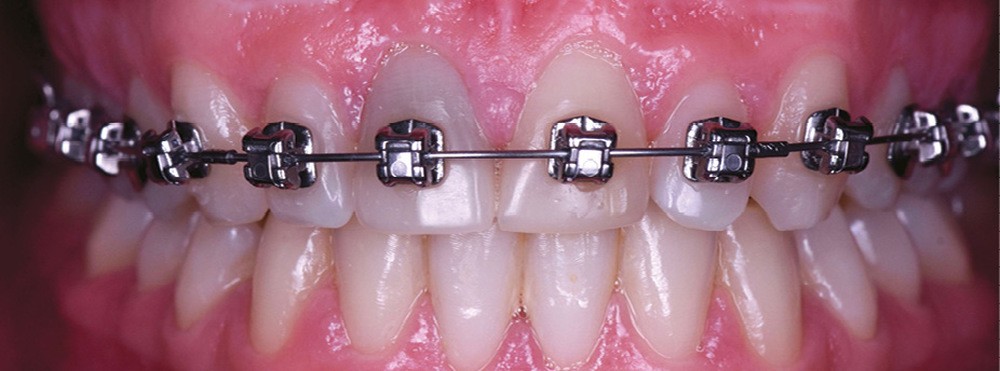

– la nécrose, qui va donner une coloration plutôt brune [3] (fig. 1, 2) ;

– le trauma, qui va donner une couleur plutôt rouge [4] (fig. 3) ;